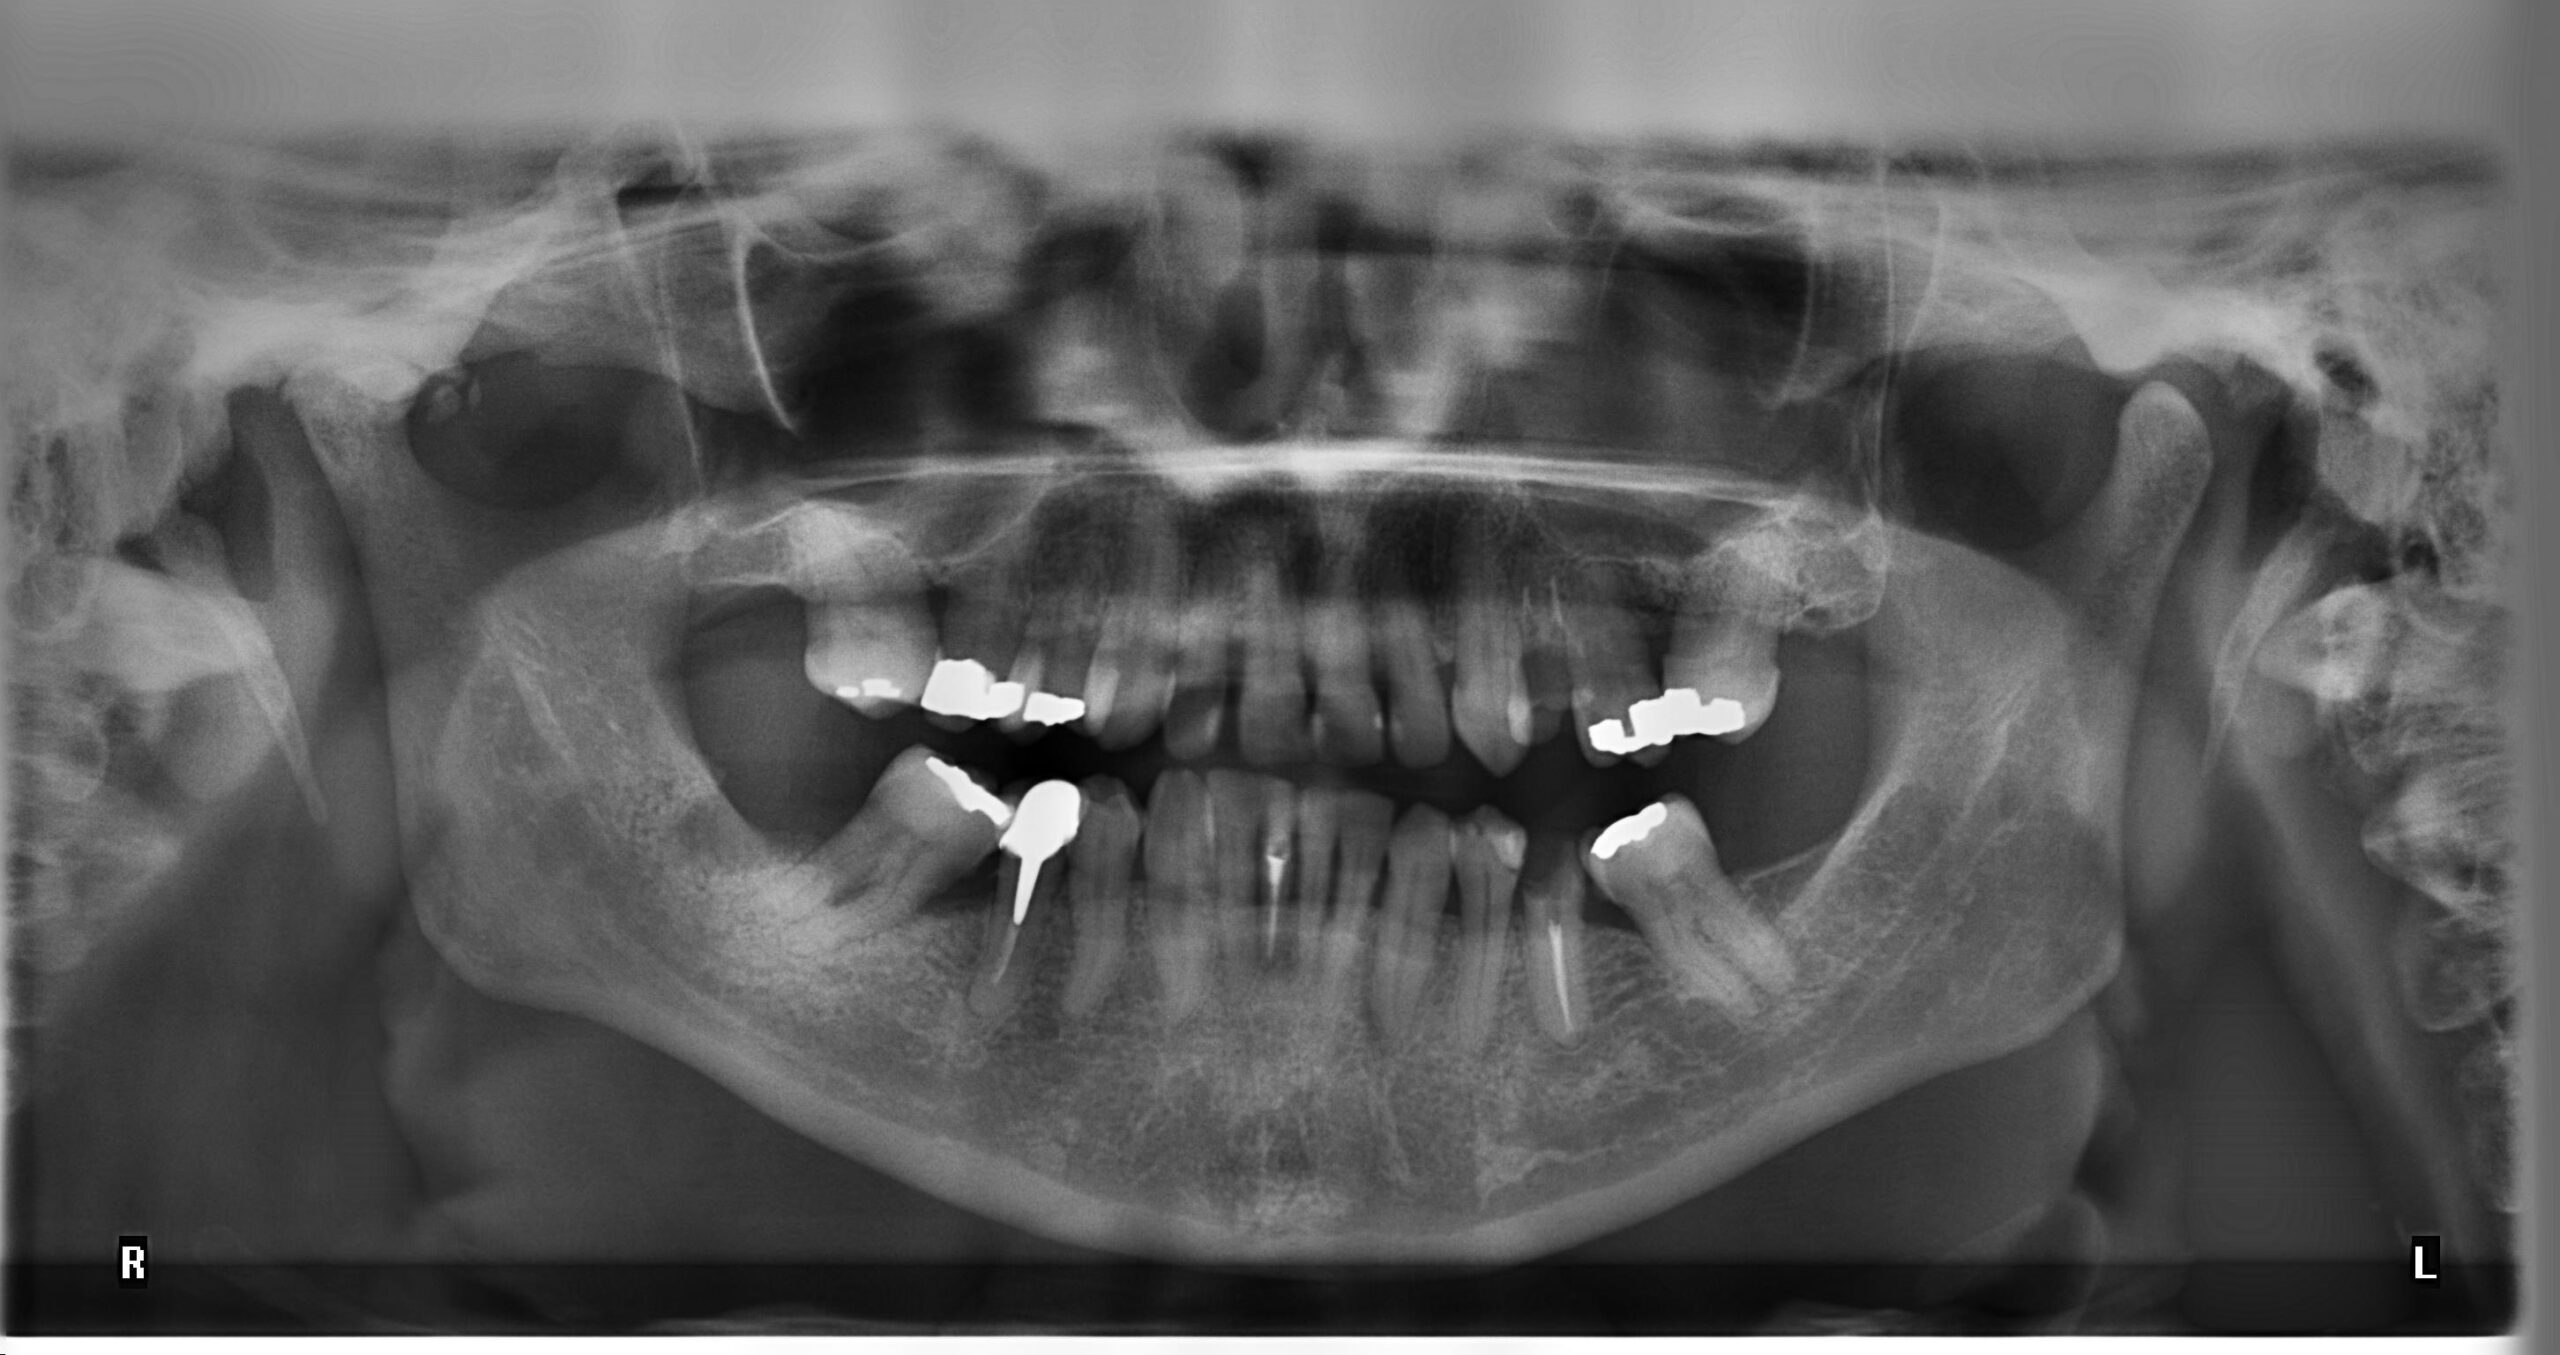

CTとはComputed Tomographyの略。

一般的な白黒の2Dレントゲンとは違い、断層写真を撮れることが従来のものとCTレントゲンの大きな違いです。

主にインプランとや親知らずの抜歯、矯正歯科治療などに用いられます。

歯ぐきの中に埋没している歯の状況や、歯ぐきや骨の厚さなども正確に分かるため、医療に大きく役立っています。

歯医者さんの中でも評価の高い歯科用CT「AUGE SOLIO(オージェソリオ)」を導入しております。

歯科用に特化したCTの為、医科用CTに比べて10分の1程度の放射線量で高精度な撮影ができます。

・3Dでの立体的な撮影が可能

・歯の下にある神経の正確な場所が分かる

・骨密度、骨の水分量が分かる

・放射線量が少なく成人、小児も安心して撮影が可能

・パノラマ画像の歪みがほとんどない

親知らずの抜歯、根管治療、矯正歯科治療やイオンプラント治療には有効です。また、患者さんに視覚的な把握と治療説明にも大変役立ちます。